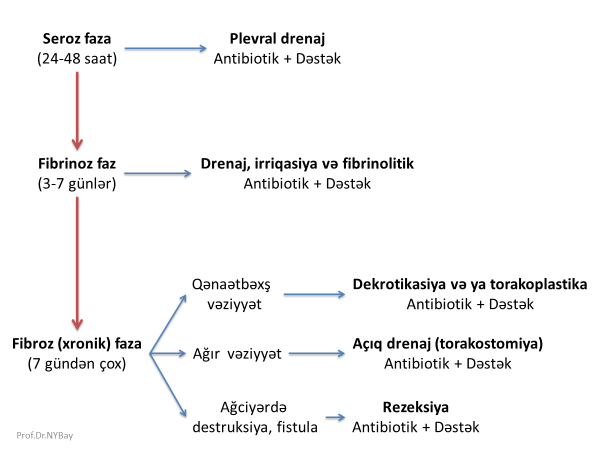

Şəkil 1. Birinci pillə müayinələrin nəticələri

Birinci pillə müayinələrdə məqsəd plevrada təcili cərrahi xəstəliyin olub-olmamasını, maye, kütlə və fistula kimi üzvi dəyişikliklərin olub-olmamasını müəyyənləşdirməkdir. Bunun üçün hərtərəfli klinik müayinə, hemoqram, Rentgen və USM edilir. Birinci pillə müayinələrdən bir neçə nəticə ortaya çıxa bilər (Şəkil 1):

- Təcili xəstəliklər

- Plevral maye

- Plevrada törəmə

- Döş divarında fistula